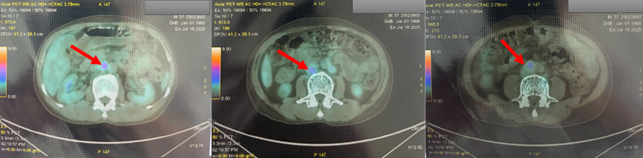

Chụp cắt lớp phát xạ positron PET/CT:

- Hình ảnh vài hạch thượng đòn trái (SUVmax: 2.85), nhiều hạch ổ bụng (SUVmax: 4.89), hạch chậu hai bên (SUVmax: 4.66) tăng chuyển hóa FDG tương ứng với hạch ác tính. Đối chiếu với mô bệnh học, hóa mô miễn dịch.

- Hình ảnh tổn thương khuyết xương ở thân đốt sống L4, xương chậu phải, xương mu phải, tăng chuyển hóa FDG khả năng ác tính (SUVmax: 3.08).

Hình 3. Hình ảnh nhiều hạch ổ bụng (SUVmax: 4.89) tăng chuyển hóa FDG tương ứng với hạch ác tính (mũi tên đỏ). Đối chiếu với mô bệnh học, hóa mô miễn dịch.

Hình 4. Hình ảnh tổn thương xương chậu phải (mũi tên màu da cam), xương mu phải (mùi tên màu vàng), tăng chuyển hóa FDG khả năng ác tính (SUVmax: 3.08); hạch bẹn 2 bên tăng chuyển hóa FDG, với tổn thương có kích thước lớn và tăng bắt FDG rõ rệt ở hạch bẹn phải (mũi tên vàng), SUVmax: 4,66.

Kết quả PET/CT toàn thân của bệnh nhân tuy không phát hiện được tổn thương nguyên phát, nhưng phát hiện được rất nhiều các tổn thương di căn hạch trong ổ bụng-tiểu khung như nhiều hạch cạnh động mạch chủ, hạch dọc bó mạch chậu 2 bên với kích thước lớn và SUVmax cao, ngoài ra còn có xương đốt sống, cánh chậu, và gan. Với những thông tin có được từ PET/CT, bác sĩ lâm sàng có thể lựa chọn các vị trí khác nhau để sinh thiết lại tổn thương tìm nguồn gốc u (ví dụ: xương, gan). Đồng thời cũng đặt ra cân nhắc về nội soi tai mũi họng lần thứ hai để khẳng định lại tính chất của tổn thương amidan phải phát hiện trên PET/CT nhưng chưa nhìn được trong nội soi tai mũi họng lần đầu tiên.